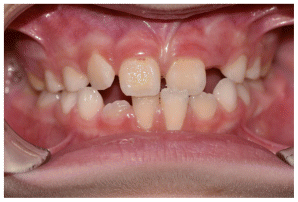

The patient was a growing female child who presented during early mixed dentition with an anterior crossbite associated with a deep overbite and a marked sagittal discrepancy (Figures 12–19). The initial clinical examination revealed a negative overjet, complete anterior deep bite, and a functional Class III occlusal pattern. Extraoral assessment showed a flattened facial profile, while cephalometric analysis confirmed a skeletal imbalance characterized by increased SNA and SNB values, an ANB of 0°, negative Withs appraisal, and significant dentoalveolar compensations, including proclination of both upper and lower incisors (Table 3). The vertical pattern was predominantly hypodivergent, suggesting a high risk of unfavorable mandibular growth progression if left untreated. Given the patient’s young age and growth potential, an early interceptive treatment was planned to use the AMCOP® TC appliance, with the aim of correcting the anterior crossbite, improving neuromuscular balance, and guiding sagittal and vertical development during growth. The appliance was worn nightly and for additional daytime hours, according to patient compliance.

After 18 months of treatment, a clear clinical improvement was observed. Intraoral examination demonstrated complete correction of the anterior crossbite, with establishment of a positive overjet and normalization of the anterior occlusal relationship. The deep bite was reduced, allowing more functional anterior guidance. Occlusal relationships improved toward a stable dental Class I, and the need for excessive dentoalveolar compensation was reduced. Cephalometric reassessment showed an overall improvement in sagittal relationships and incisor inclinations, with a trend toward normalization of the previously altered parameters. These findings indicate that early functional therapy with the AMCOP® TC appliance was effective in intercepting the developing Class III malocclusion, improving occlusal function, and potentially reducing the severity of future skeletal discrepancies (Table 4).